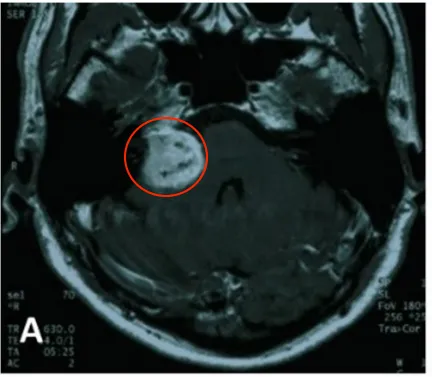

2004年5月,患者确诊为听神经瘤并接受首次开颅手术。术后病理检查确认诊断,初期治疗显示右侧桥小脑角区肿瘤呈现不均匀强化表现。为控制术后残留病灶,2005年8月实施伽玛刀治疗。2007年5月随访发现肿瘤再次进展,遂行第二次开颅手术。

2004年4月初始MRI显示右侧桥小脑角区肿瘤不均匀强化。2005年8月首次术后、伽玛刀治疗前影像资料记录肿瘤状态。2007年5月第二次术前MRI评估显示肿瘤进展,术后一个月影像确认切除范围。